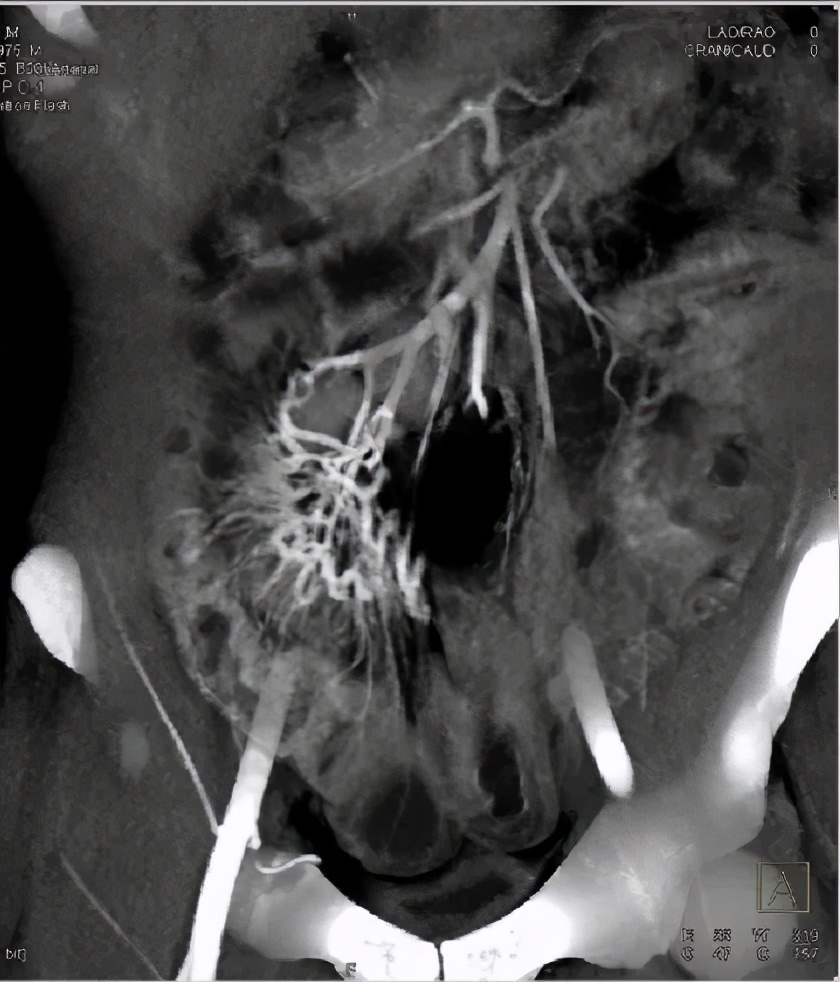

克罗恩病的确诊与治疗都是极其复杂的,如果怀疑克罗恩病,医生可能需要通过血液检查、粪便检查和结肠镜、胃镜或小肠胶囊内镜、小肠X线拍片、磁共振(MRI)肠造影等多项检查,才能做出最后的判断。